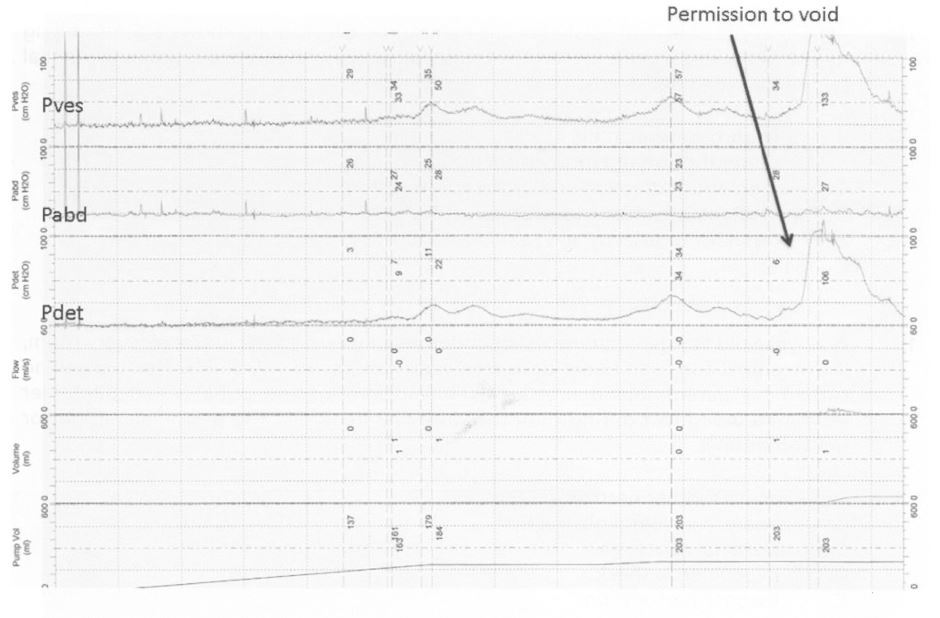

67-year-old man has bothersome LUTS six months after hip surgery despite tamsulosin treatment. His urinalysis shows 0-2 RBC/hpf, and his PVR is 90 ml. DRE demonstrates 35 gm prostate. He undergoes urodynamics as shown. The next step is:

E

This patient has urodynamically demonstrable bladder outlet obstruction. While antimuscarinics may help his irritative symptoms (e.g.,frequency, urgency, urge incontinence), it will not address his primary obstructive problem, and indeed, may worsen his symptoms. Obtaining a serum creatinine is not useful or recommended in the BPH guidelines for work-up of LUTS. Cystoscopy may help assess prostatic size, but would be unlikely to change management as his DRE shows a 35 gm prostate on exam. OnabotulinumtoxinA injections are not approved for, nor do they have documented efficacy for the treatment of LUTS related to bladder outlet obstruction. In this patient, TURP is the next step for the treatment of bladder outlet obstruction.